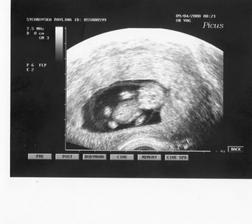

A pokračujeme dál : 17.4.2008 jsme navštívili nemocnici v Ústí nad Labem kvůli srdíčku miminka,zda nemá po manželovi vrozenou vadu,prozatím je vše v pořádku,ale 19.6.2008 jedeme na kontrolu.